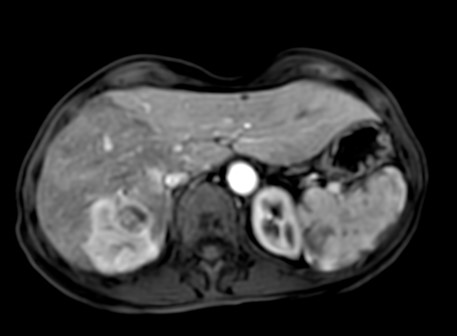

Participants will be presented with cases of atypical focal nodular hyperplasia and hemangiomas with different MR contrast agents, along with cases of epithelioid hemangioendothelioma, angiosarcoma, angiomyolipoma, fibrolamellar hepatocellular carcinoma, infiltrating hepatocellular carcinoma and neoplastic portal vein thrombosis, peribiliary cysts, multiacinar regenerative nodules, focal confluent fibrosis.

Formal lectures will be presented, followed by a case-based review of challenging cases encountered in clinical practice, simulating the reading room experience, to develop appropriate skills for the differential diagnosis of patients with hepatic diseases. Each day, attendees will be provided with approximately 20 cases to review independently, and then jointly to fine-tune their ability to recognize and characterize liver lesions.